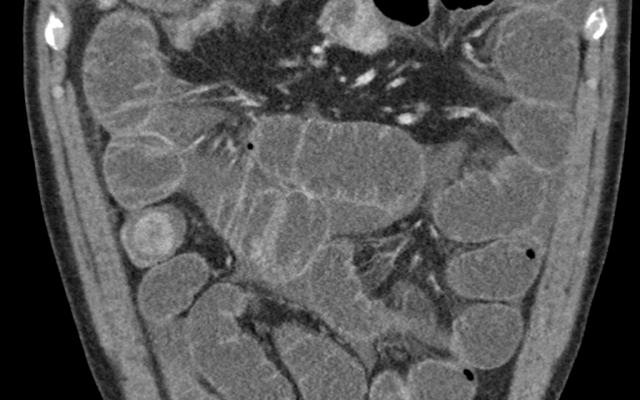

Een 57-jarige man kwam op de SEH met koorts, pijn links onder in de buik en het uitblijven van ontlasting sinds een dag. De voorgeschiedenis van patiënt vermeldde diverticulitis en cholecystitis waarvoor hij galblaasdrainage had ondergaan. Bij lichamelijk onderzoek was zijn buik links onder fors drukpijnlijk. Laboratoriumonderzoek toonde verhoogde ontstekingsparameters. Differentiaaldiagnostisch dachten wij aan een al dan niet gecompliceerde diverticulitis. De CT-scan van het abdomen toonde echter een verdikte galblaaswand en een – relatief zeldzame – fistel tussen de galblaas en het colon transversum (figuur 1a). Tevens was er sprake van pneumobilie, het belangrijkste röntgencriterium voor een galsteenilieus. In…